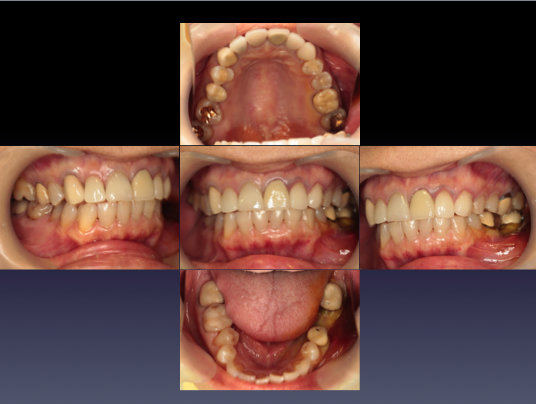

症例⑤

上左右の奥歯を失ってしまったため、保険の入れ歯を入れたが、違和感が強く、しっかり噛むことができないため、インプラントを併用した入れ歯を作ることで違和感なく、しっかり噛むことができるようになった。 また通常の入れ歯は、はずれないようにするため金属のバネを歯に引っ掛けるため見た目も悪いが、インプラントによって固定されているためバネもなく、見た目も非常に良いものとなっている。

術前

-

術前レントゲン写真